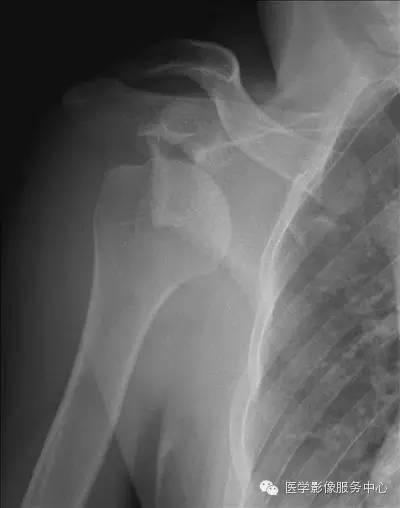

患者中年男性,46岁,以"右肩关节酸痛不适18个月"为主诉入院.

术前清晰的肩关节ct冠状位.

术前完善检查行肩关节ct平扫 三维重建及肩关节磁共振辅助诊断.

62岁男性跌倒后,肩膀越来越痛,原因竟是